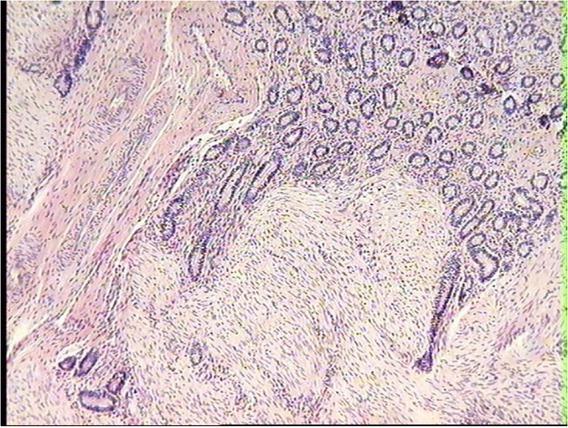

Uterus histopathological changes. In all examined uterus specimens, pathological changes characteristic of the adenomyosis disease process were diagnosed. They were the proliferation of basal mucosal glands, and mucosa interstitial tissue, atrophy of glands of the superficial mucosa layer, and small foci of inflammatory cell infiltration in the mucosa layer (Figs 1, 2, 3). Among the examined cows, these types of pathological changes were found to highly varying degrees.

Proliferation of mucosal basal glands into the muscular layer in the uterus of dairy cow. HE, 10×